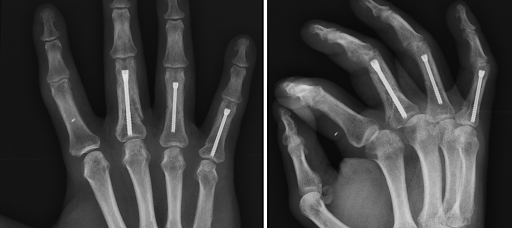

¿Dolor súbito en el codo y pérdida de fuerza al doblar el brazo o girar el antebrazo? Puede tratarse de una rotura del bíceps distal. Con técnicas quirúrgicas mini invasivas, es posible reparar el tendón con incisiones mínimas, menor dolor y una recuperación más rápida.